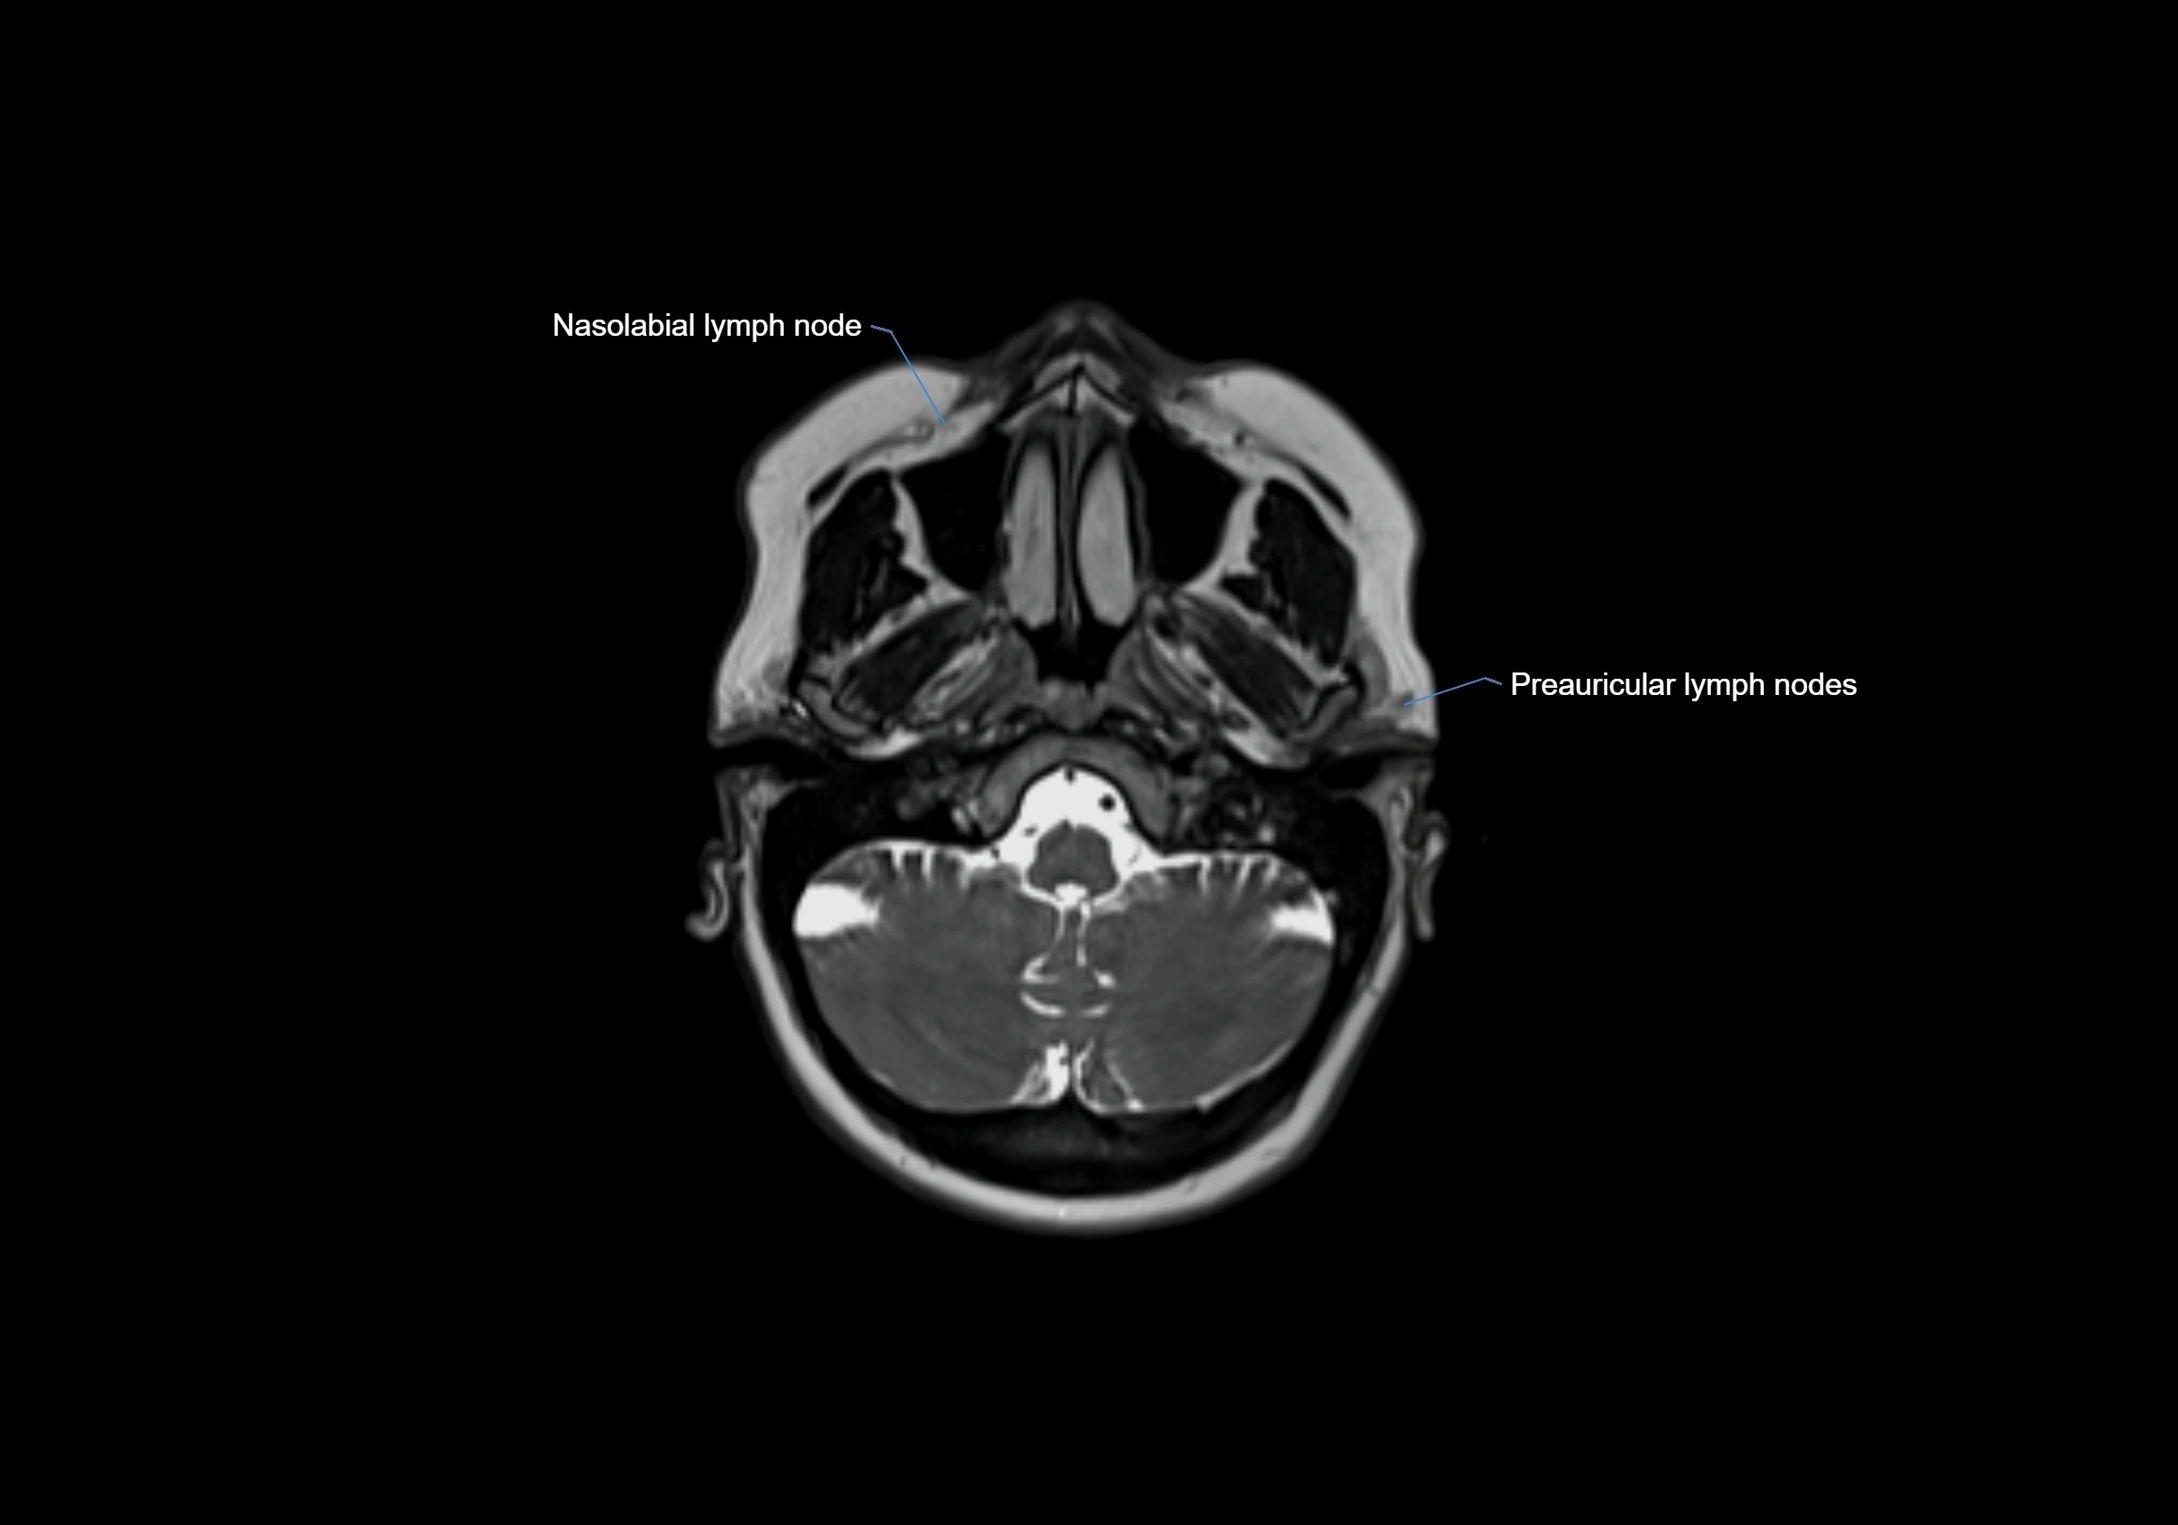

Accessory lymph nodes are small, secondary lymph nodes located along the main facial and cervical lymphatic chains, often adjacent to primary lymph nodes, such as preauricular, submandibular, or occipital nodes. They are typically less than 5 mm in diameter, embedded within subcutaneous fat or connective tissue, and may be variable in number and location. These nodes provide additional filtration and immune surveillance for lymph collected from the face, scalp, and neck regions. Accessory lymph nodes are usually non-palpable in healthy individuals but may enlarge in response to infection, inflammation, or metastasis, making them clinically significant.

• Found along primary lymph node chains, including preauricular, submandibular, parotid, and occipital regions

MRI Appearance

T1-weighted images:

• Normal accessory nodes appear as small, oval hypointense to intermediate signal structures within subcutaneous fat

• Surrounded by hyperintense fat, enhancing contrast for visualization

• Pathological nodes may appear enlarged or rounded, sometimes with cortical thickening

T2-weighted images:

• Nodes show intermediate signal, with surrounding fat bright

• Useful for detecting edema, inflammation, or infiltration

• Fatty hilum may appear slightly hyperintense relative to cortex